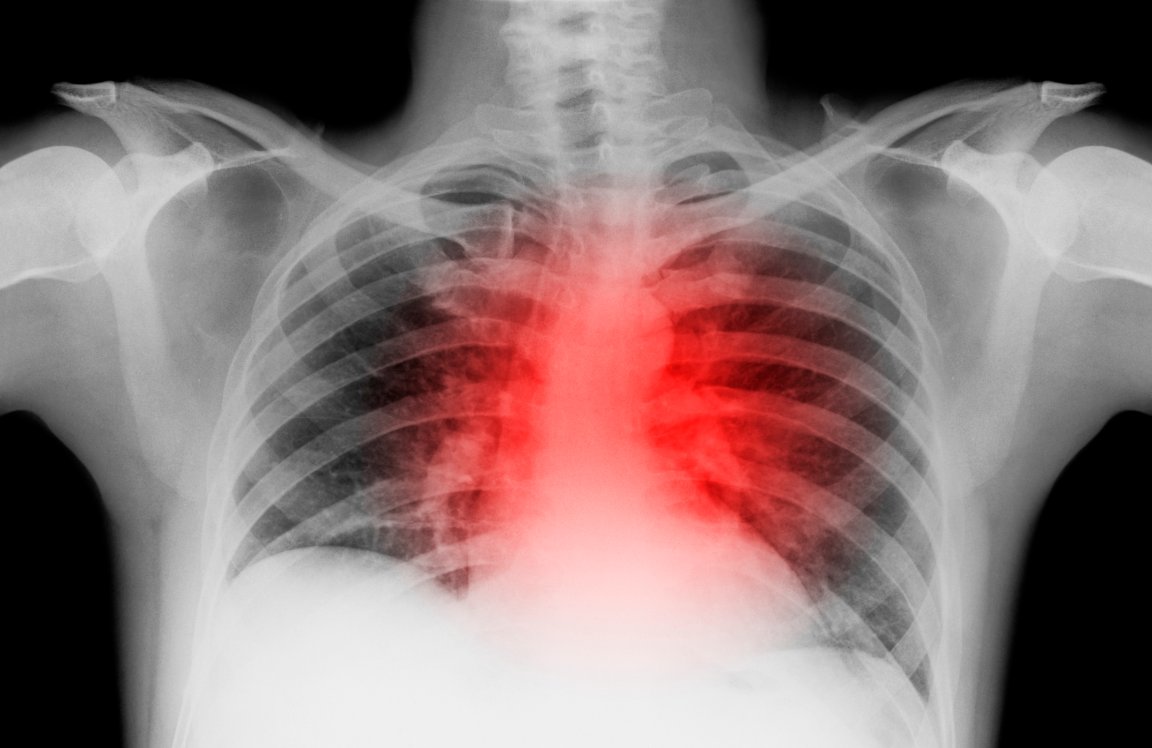

Contrary to its name, heart failure (also known as congestive heart failure) is not a condition in which the heart suddenly stops beating. Instead, it’s a condition in which the heart is unable to pump enough blood and oxygen to the rest of the body. It’s most likely to occur in those who have experienced a heart attack, during which blood and oxygen cease to flow to the heart. This lack of oxygen causes part of the heart muscle to die and be replaced by dead scar tissue, known as fibroblasts. Over time, the heart weakens to the point of being completely unable to support the body.